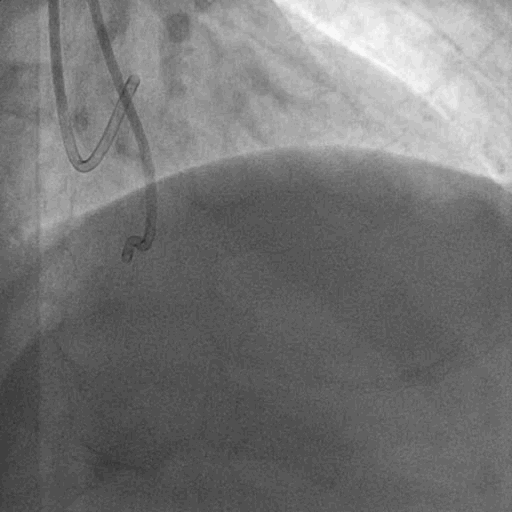

双侧造影: